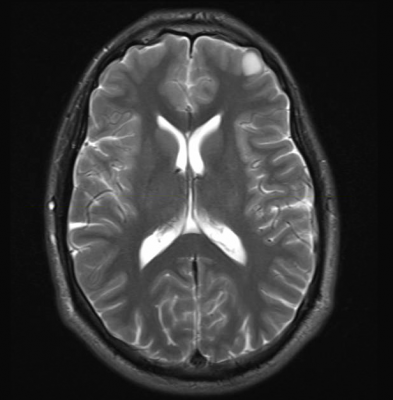

More than 1.8 million people will be diagnosed with lung cancer worldwide this year. Up to 30 percent of NSCLC will eventually spread to the brain, and most are inoperable and have a poor prognosis. Secondary brain tumors are usually treated with whole brain radiotherapy along with supportive care including steroids (usually dexamethasone), but with limited success.

In order to see if patients could be treated as effectively without whole brain radiotherapy (WBRT), Mulvenna and colleagues designed the non-inferiority Quality of Life after Treatment for Brain Metastases (QUARTZ) trial. They recruited 538 NSCLC patients (aged 18 or older) with brain metastases from 69 centers in the U.K. and three in Australia between March 2007 and August 2014. Participants were randomly assigned to receive either best supportive care and dexamethasone, or best supportive care and dexamethasone plus whole brain radiotherapy (20 Gy in five daily fractions).